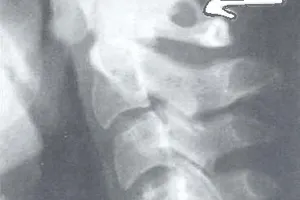

Аномалия Киммерли – это патологическое изменение атланта, первого шейного позвонка. Заболевание наиболее распространенно как врожденный порок развития, встречается также аномалия Киммерли в форме заболевания, приобретенного в течение жизни. Аномалия Киммерли — наличие в структуре первого шейного позвонка дополнительной костной дужки, ограничивающей движения позвоночной артерии и вызывающей синдром ее сдавления. Аномалия Киммерли характеризуется головокружением, шумом в ушах, шаткостью походки и расстройством координации, «мушками» и потемнением в глазах, приступами потери сознания и внезапной мышечной слабости. Возможны двигательные и чувствительные расстройства, возникновение ТИА и ишемического инсульта. Диагностируется аномалия Киммерли при рентгенографическом исследовании краниовертебрального перехода, проведении магнитно-резонансной ангиографии, дуплексного сканирования и УЗДГ сосудов головы и шеи. Сосудистые нарушения, которыми сопровождается аномалия Киммерли, подлежат комплексному консервативному лечению. Операция по резекции аномальной дуги производится лишь в тяжелых случаях. Наряду с аномалией Киари, платибазией и ассимиляцией атланта аномалия Кимерли относится к так называемым краниовертебральным мальформациям — врожденным нарушениям строения области сочленения черепа с первыми шейными позвонками. По некоторым данным аномалия Киммерли встречается у 12-30% людей. Вызывая сдавление позвоночной артерии, аномалия Киммерли сопровождается хронической ишемией в задних отделах мозга. Однако такая ситуация возникает далеко не всегда. Сама по себе аномалия Киммерли не является заболеванием , и ее наличие не говорит о том, что именно она вызывает сосудистые нарушения в бассейне позвоночной артерии. При обследовании пациентов, у которых имеется синдром позвоночной артерии и аномалия Киммерли, лишь у 25% обнаруживается причинно-следственная связь между наличием аномалии и развитием синдрома. Патогенез сосудистых нарушений при аномалии Киммерли Правая и левая позвоночные артерии отходят от соответствующих подключичных артерий. Каждая позвоночная артерия проходит вдоль шейного отдела позвоночника, находясь в канале, образованном отверстиями поперечных отростков его позвонков. Затем она входит в большое затылочное отверстие, попадая таким образом в полость черепа. Позвоночные артерии и их ветви образуют так называемый вертебрально-базилярный бассейн, кровоснабжающий часть спинного мозга в шейном отделе позвоночника, мозжечок и ствол мозга. Выходя из шейного канала, позвоночная артерия огибает шейный позвонок и горизонтально проходит в широкой костной борозде, где она может свободно перемещаться при движениях головы. Костная дужка, наличием которой характеризуется аномалия Киммерли, расположена над костной бороздой и ограничивает движения позвоночной артерии в этом месте. Аномалия Киммерли может приводить к развитию синдрома позвоночной артерии двумя путями: за счет срабатывания периваскулярных вегетативно-ирритативных механизмов симпатической иннервации и за счет уменьшенного поступления крови в вертебрально-базилярный бассейн из-за механического сдавления позвоночной артерии. Факторами, приводящими к тому, что аномалия Киммерли становиться клинически значимой, являются атеросклероз, поражение сосудистой стенки при васкулитах, шейный спондилоартроз, остеохондроз шейного отдела позвоночника, артериальная гипертензия, наличие других краниовертебральных мальформаций, рубцовый процесс, черепно-мозговая травма или травма позвоночника с повреждениями в области краниовертебрального перехода. К возникновению клинической картины синдрома позвоночной артерии у пациентов с аномалией Киммерли могут приводить травмы плеча, вызывающие повреждение ограниченной костной дужкой позвоночной артерии по хлыстовому механизму. Классификация аномалии Киммерли В неврологии выделяют 2 вида аномалии Киммерли. Первая характеризуется наличием костной дужки, соединяющей суставной отросток атланта с его задней дугой. Во втором варианте аномалия Киммерли представлена костной дужкой между суставным отростком атланта и его поперечным отростком. Аномалия Киммерли может иметь односторонний характер или наблюдаться с обоих сторон первого шейного позвонка. Кроме того, аномалия Киммерли может быть полной и неполной. Полная аномальная костная дужка имеет вид полукольца, неполная костная дужка представляет собой дугообразный вырост. Симптомы аномалии Киммерли Клинические проявления, которыми сопровождается аномалия Киммерли, обусловлены уменьшенным притоком крови к задним отделам головного мозга. В результате пациенты испытывают шум в ухе или обоих ушах (свист, звон, гул, шипение), мелькание «мушек» или мерцание «звездочек» перед глазами, внезапное преходящее потемнение в глазах. Указанные симптомы усиливаются при поворотах головы. Поскольку аномалия Киммерли сопровождается нарушением кровоснабжения мозжечка, то возникают головокружение и шаткость походки, которые также могут усугубляться при поворотах головой. На фоне некомфортного положения головы или перенапряжения мышц шеи при аномалии Киммерли у пациентов могут наблюдаться приступы потери сознания. Возможна внезапно возникающая мышечная слабость, приводящая к падению больного без потери сознания. В случаях более тяжелого течения аномалия Киммерли может сопровождаться головной болью, тремором рук и ног, нистагмом, нарушениями координации, гипестезией и/или мышечной слабостью части лица или туловища, чувствительными и двигательными расстройствами одной или нескольких конечностей. Могут наблюдаться транзиторные ишемические атаки в вертебрально-базилярном бассейне. Особо тяжелым осложнением наличия аномалии Киммерли является ишемический инсульт. Диагностика аномалии Киммерли При обращении пациента с симптомами недостаточности кровообращения в вертебрально-базилярном бассейне головного мозга в первую очередь производят рентгенографию черепа и рентгенографию позвоночника в шейном отделе. Аномалия Киммерли, как правило, достаточно четко визуализируется на боковых рентгенограммах области краниовертебрального перехода. При наличие ушного шума для исключения лор-патологии (кохлеарный неврит, хронический средний отит, лабиринтит) может потребоваться консультация отоларинголога, проведение аудиометрии и других исследований слуха. Производится также исследование вестибулярного анализатора (вестибулометрии, электронистагмографии, стабилографии). Поскольку выявленная аномалия Киммерли может не являться причиной синдрома позвоночной артерии, неврологу необходимо исключить другие возможные причины вертебрально-базилярной недостаточности. Выявить тромбоз, артерио-венозную мальформацию или аневризму сосудов головного мозга, сдавление сосуда объемным образованием (опухоль, киста или абсцесс головного мозга) способна контрастная ангиография. Определить насколько клинически значима аномалия Киммерли, т. е. степень ее влияния на кровообращение в вертебрально-базилярном бассейне, позволяет применение целого ряда гемодинамических исследований: УЗДГ экстракраниальных сосудов, транскраниальной допплерографии, дуплексного сканирования и магнитно-резонансной ангиографии сосудов головного мозга. С их помощью при аномалии Кимерли возможно выявить локализацию сдавления позвоночной артерии и ее зависимость от положения головы и шеи. Лечение аномалии Киммерли Аномалия Киммерли требует лечения в случае наличия клинических и гемодинамических признаков нарушения кровообращения в вертебрально-базилярном бассейне, связанного именно с данной патологией. Пациенты, у которых имеется аномалия Киммерли, должны соблюдать некоторые меры предосторожности в рамках охранительного режима. При аномалии Киммерли следует избегать форсированных физических нагрузок, резких поворотов головой, стоек на голове, кувырков, спортивных занятий и игр, связанных с ударами головой (борьба, футбол, спортивная гимнастика и пр.). При прохождении массажа или мануальной терапии шейного отдела позвоночника пациенту необходимо предупреждать массажиста и мануального терапевта о том, что у него аномалия Киммерли. Ухудшение состояния пациента является поводом к незамедлительному обращению к врачу. В большинстве случаев аномалия Киммерли, приводящая к клиническим проявлениям сосудистой недостаточности, подлежит консервативному лечению. Проводится сосудистая терапия направленная на улучшение мозгового кровотока. По показаниям под контролем коагулограммы при аномалии Кимерли применяются препараты, улучшающие реалогические свойства крови. В комплексную терапию включают также антиоксиданты, ноотропы, нейропротекторы и метаболические препараты. Аномалия Киммерли на сегодняшний день не является показанием для проведения хирургического лечения. Необходимость в оперативном лечении может возникнуть при декомпенсированном течении синдрома позвоночной артерии, приводящем к выраженной недостаточности кровообращения в вертебрально-базилярном бассейне при отсутствии достаточного коллатерального кровоснабжения. Операция при аномалии Киммерли заключается в резекции аномальной дуги и мобилизации позвоночной артерии. В послеоперационном периоде пациентам необходимо ношение воротника Шанца сроком от 2 до 4 недель.

Лицам с нарушением кровообращения в вертебробазилярном бассейне головного мозга при обращении к специалисту назначается рентгенографию черепа и рентгенографию позвоночника в шейном отделе. Также может потребоваться обследование отоларинголога для исключения ЛОР-патологии. Помимо этого, больному может быть назначена вестибулометрия, электронистагмографии или стабилографии.

На рентгеновских снимках аномалия Кимерли четко визуализируется на боковых рентгенограммах области краниовертебрального перехода (видны дополнительные костные дужки).